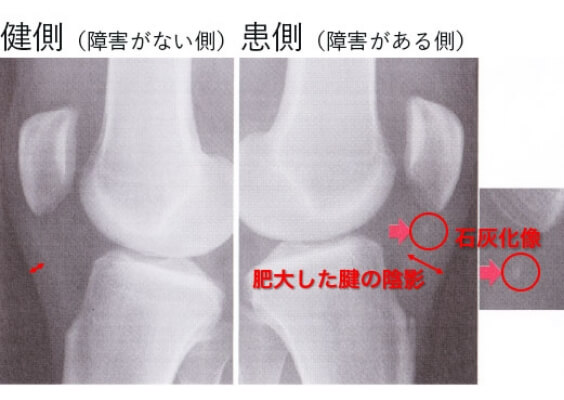

• ジャンパー膝の画像診断

X線・エコー・MRIなどを用いて診断します。

1.X線

患側(障害がある側)では健側(障害がない側)と比較して腫大した腱の陰影が認められます。赤い丸印の部分は膝蓋腱部の石灰化像です。

ジャンパー膝の画像診断(X線)